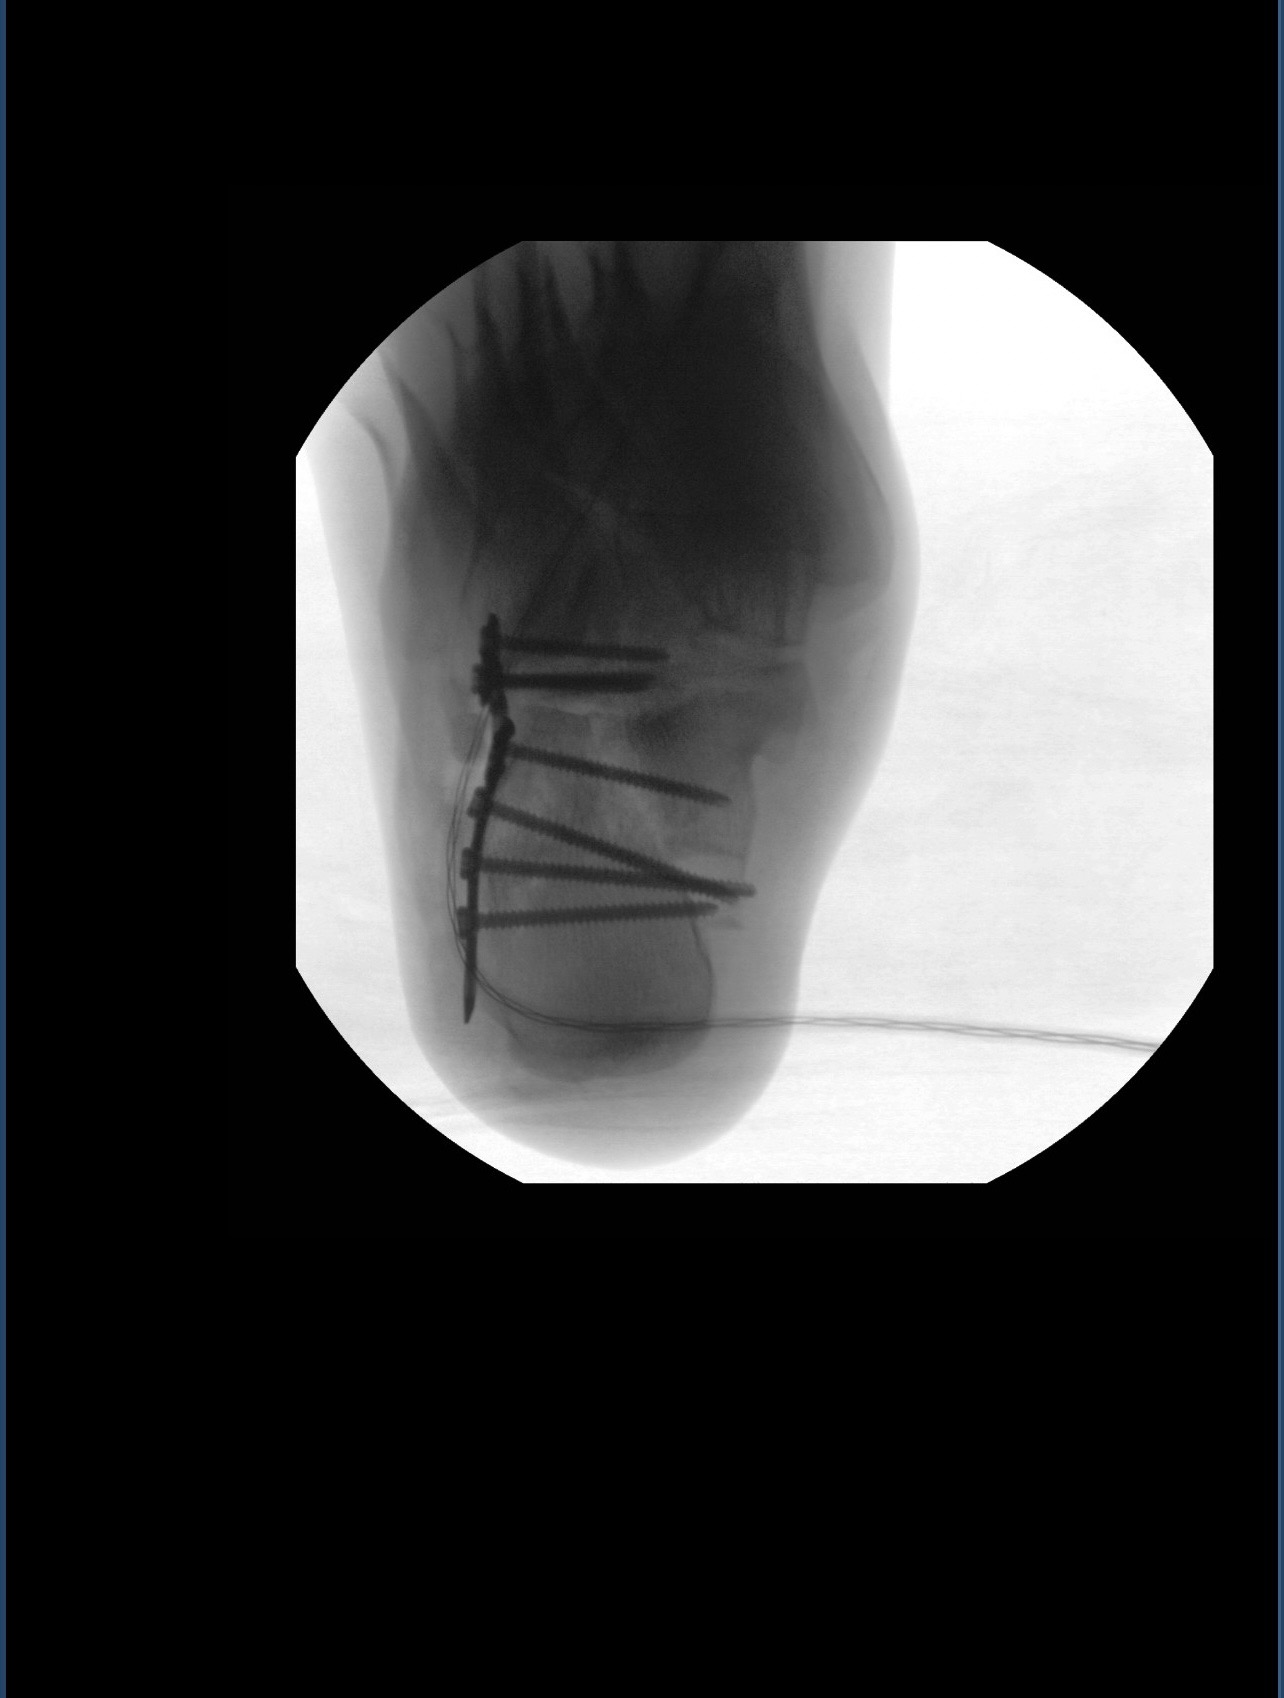

• Een verbrijzelde hiel (waar ik intussen aan geopereerd ben)